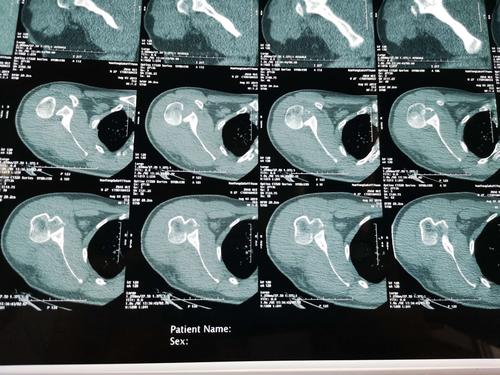

该患者行ct检查提示肩关节后脱位合并反bankart损伤 反hill-sachs

水平位ct显示肱骨头后脱位.

(肩锁关节 胸锁关节)ct平扫